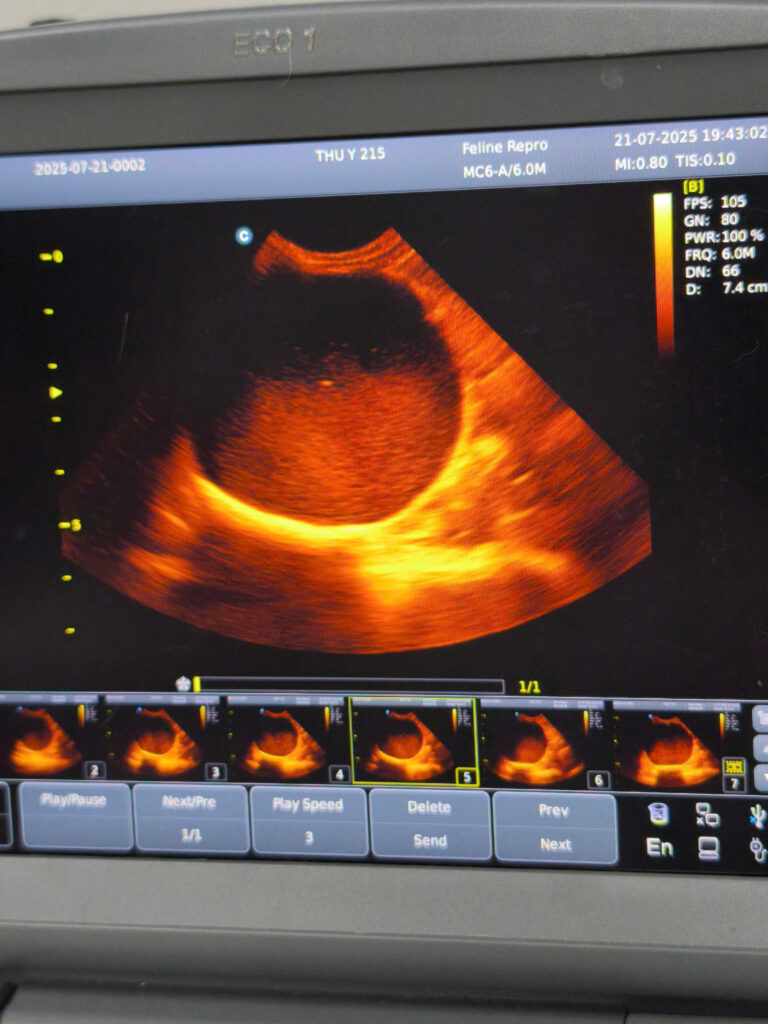

Siêu âm bàng quang và thận

Siêu âm để kiểm tra sỏi – viêm – cấu trúc niệu đạo